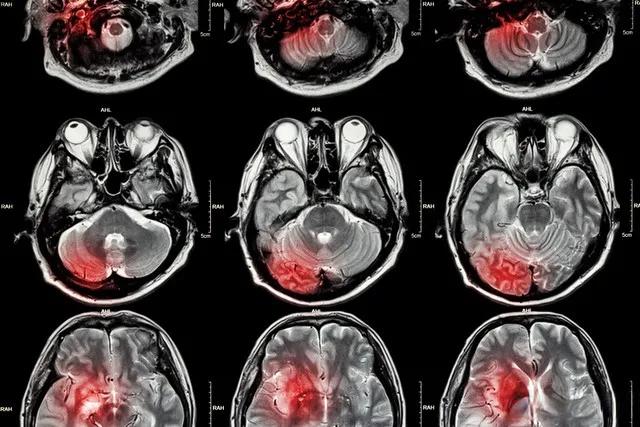

脑梗塞是一种常见的脑血管疾病,占所有急性脑血管疾病的70%。据统计,我国有3500万脑血管病患者,每年新增260万。面对如此高发的疾病,中西医各有其独特的治疗方法。